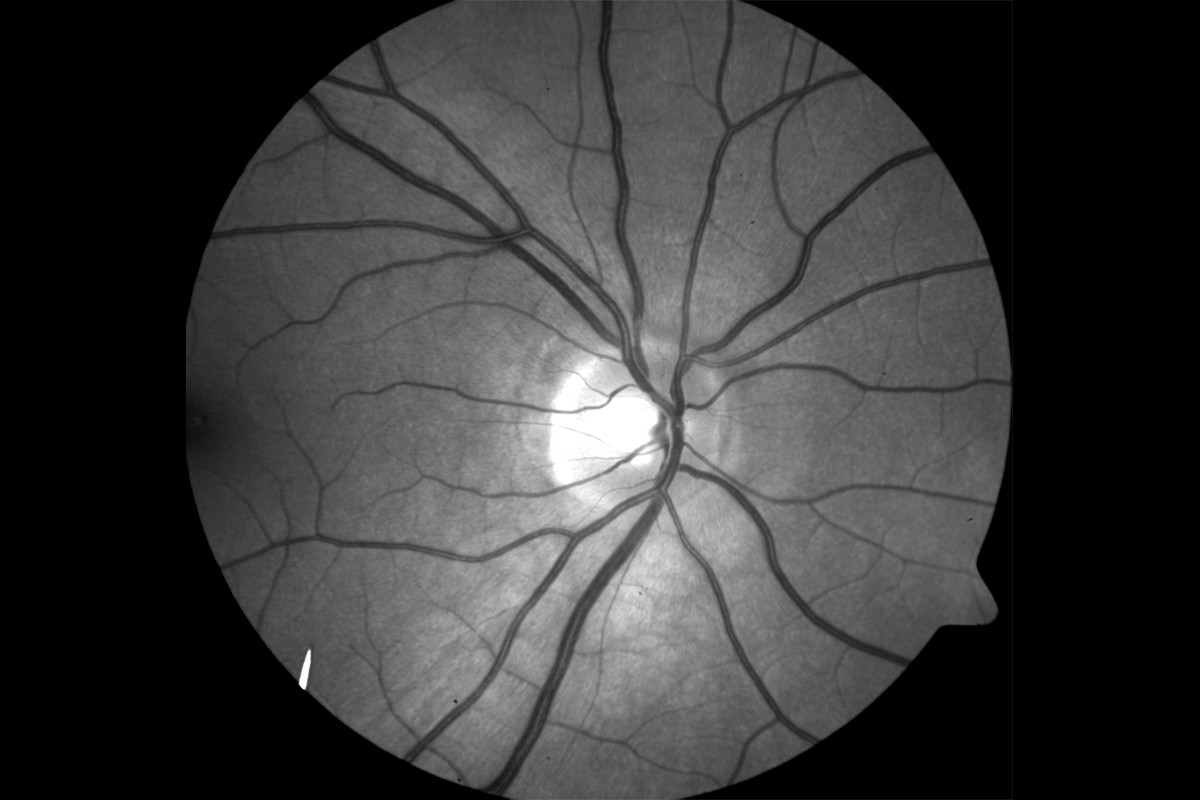

VesselMap aric: Image of the ocular fundus with measuring rangeVesselMap aric: Image of the ocular fundus with measuring range

• VesselMap aric: Image of the ocular fundusVesselMap aric: Image of the ocular fundus

1. Images from the ocular fundus are taken by using an imaging system.

2. The fundus image is opened in the software and the papilla is marked. Therefore, a measurement grid is placed on the image.

3. Subsequently, within this measurement grid (ring zone), all essential arterial and venous vessels are marked manually by selecting and clicking on them.

The recording of the fundus images, determination of the parameters and evaluation of the static vessel parameters are carried out on the basis of the ARIC study.